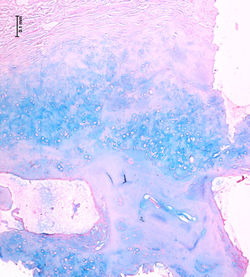

Histológicamente, se caracteriza por la presencia de lagos de mucina separados por delgados septos fibrosos (F1, 2, 5), entre los lagos se reconoce la presencia de células tumorales cuboidales de núcleo ovalado central (F3), pueden encontrarse áreas de diferenciación glandular, sólida, micropapilar (F4) o cribiforme (F5, F6)(3).

Los depósitos de mucina son positivos con la coloración de alcian blue (F7), asimismo son PAS positivos resistentes a la diastasa. En los estudios de inmunohistoquímica, las células tumorales muestran positividad para CK7 (F8), CAM 5.2, receptores de estrógenos (F9), receptores de progesterona (F10), EMA (F11) y CEA (F12) y negatividad para CK20 (F12). Se han descrito algunos casos con diferenciación neuroendocrina que expresan los marcadores cromogranina, sinaptofisina y enolasa neuronal específica, los cuales fueron negativos en nuestro caso (F12). Se pueden reconocer áreas de carcinoma in situ por la presencia de células mioepiteliales evidentes con p63 (F11) o AML.